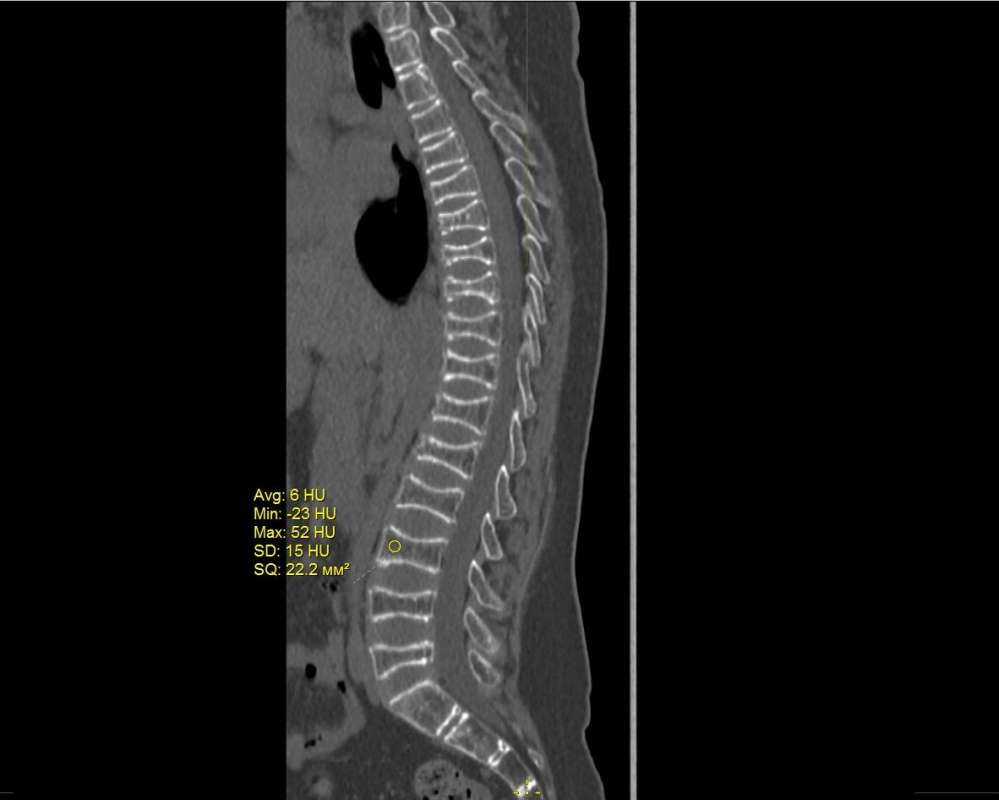

Врачи Университетской клиники ПИМУ врачи обнаружили у 12-летнего мальчика редкое генетическое заболевание — детский наследственный остеопороз.

Как сообщает пресс-служба ПИМУ, данное заболевание характеризуется склонностью к множественным переломам длинных костей и позвонков из-за снижения плотности костной ткани. Диагноз был поставлен благодаря совместной работе специалистов клиники и лаборатории наследственных болезней обмена веществ МГНЦ имени Н.П. Бочкова.

Родители обратились в клинику с проблемой компрессионных переломов позвонков грудного и поясничного отделов. Из истории болезни стало известно, что в возрасте от 1,5 до 12 лет мальчик перенёс девять переломов верхних конечностей без видимых причин. Врачи подозревали наследственное поражение скелета и провели генетический анализ, который выявил остеопороз, связанный с мутацией гена PLS3. Это заболевание встречается менее чем у одного человека из миллиона и чаще всего у мальчиков. В настоящее время проводится генетическое обследование родственников ребёнка.

Мальчик будет наблюдаться и проходить лечение в Институте педиатрии Университетской клиники ПИМУ, специализирующемся на редких заболеваниях. В настоящее время он госпитализирован, проходит комплексное обследование и получает терапию бисфосфонатами для улучшения минеральной плотности костей. Семье ребёнка были даны рекомендации по предотвращению повторения заболевания у родственников.